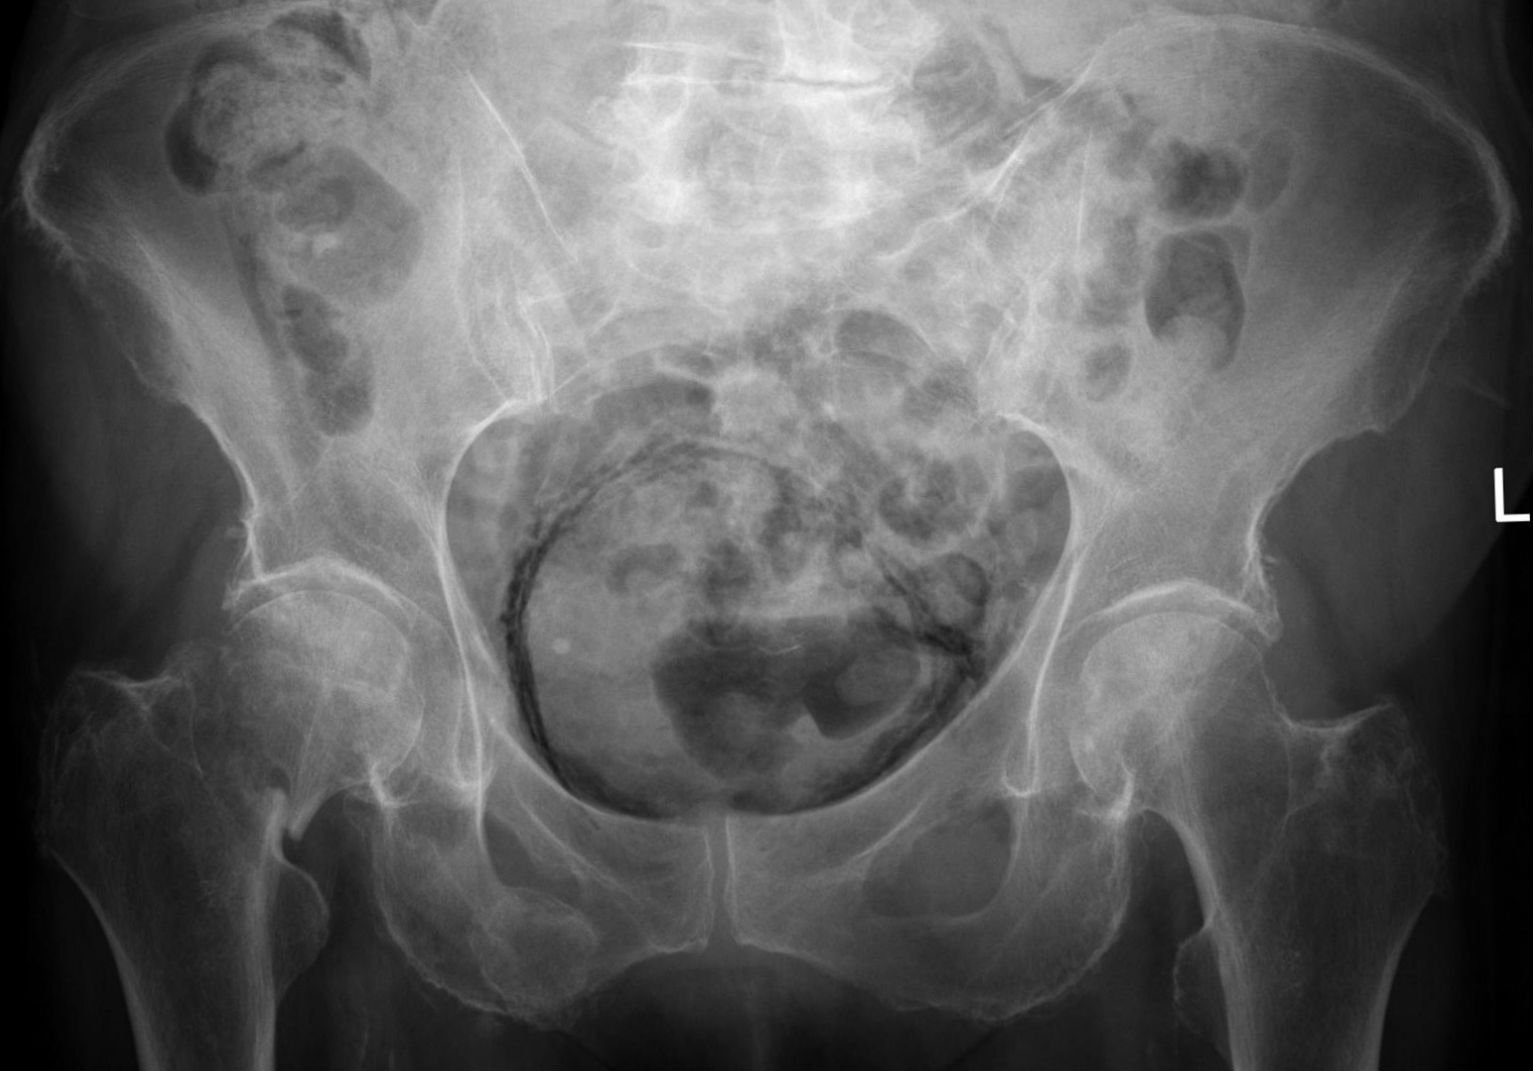

Nature: рак мочевого пузыря поражает курильщиков

Ученые из Барселоны и Вашингтона раскрыли категорию граждан, которая находится в повышенной группе риска по раку мочевого пузыря, пишет Nature.

В рамках нового исследования выяснилось, что на эволюцию клеток влияет биологический пол. Онкологическое заболевание чаще встречается у мужчин старше 55 лет.

Также анализ показал, что от рака мочевого пузыря часто страдают курильщики. Табак способствует росту измененных клеток и вызывает новые мутации. Предполагается, что новое исследование поможет в ранней диагностике рака на основе анализа мочи.

Фото: commons.wikimedia.org, Hellerhoff, Creative Commons Attribution-Share Alike 3.0 Unported license.